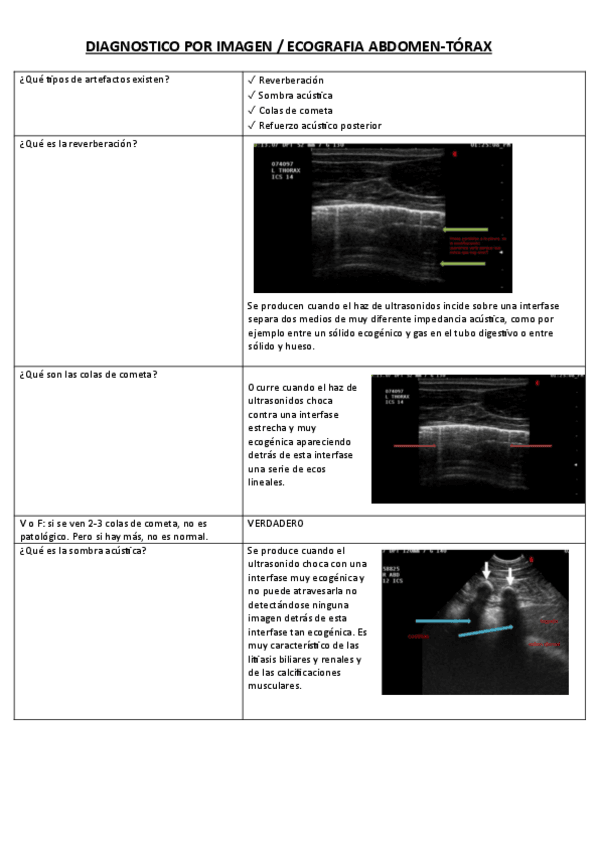

ECOGRAFIA-ABDOMEN-TORAX.pdf